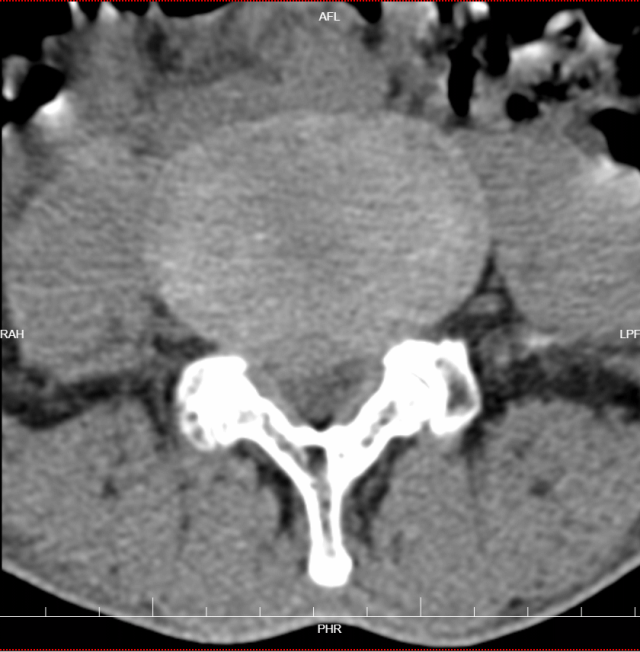

术前检查

腰椎磁共振检查显示,黄先生的腰椎间盘突出明显,神经根受压严重,这正是他症状的根源所在。